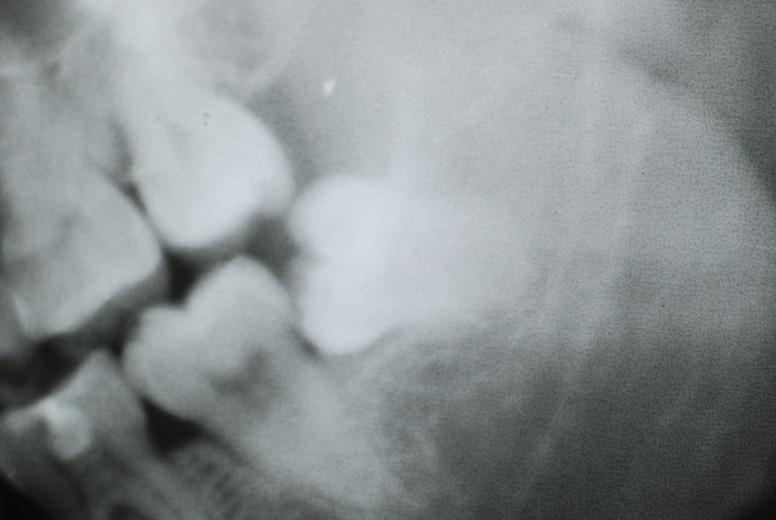

親知らずを取ることを嫌がる方が多いのですが、もし親知らずとその隣の14歳大臼歯の間に虫歯ができたり歯周病を罹患した場合、どれほど治療が大変で再発も起こりやすいか理解できない方がおおいのです。

隣の14歳大臼歯がひどい虫歯になり治療不可能になりつつある状態のレントゲン